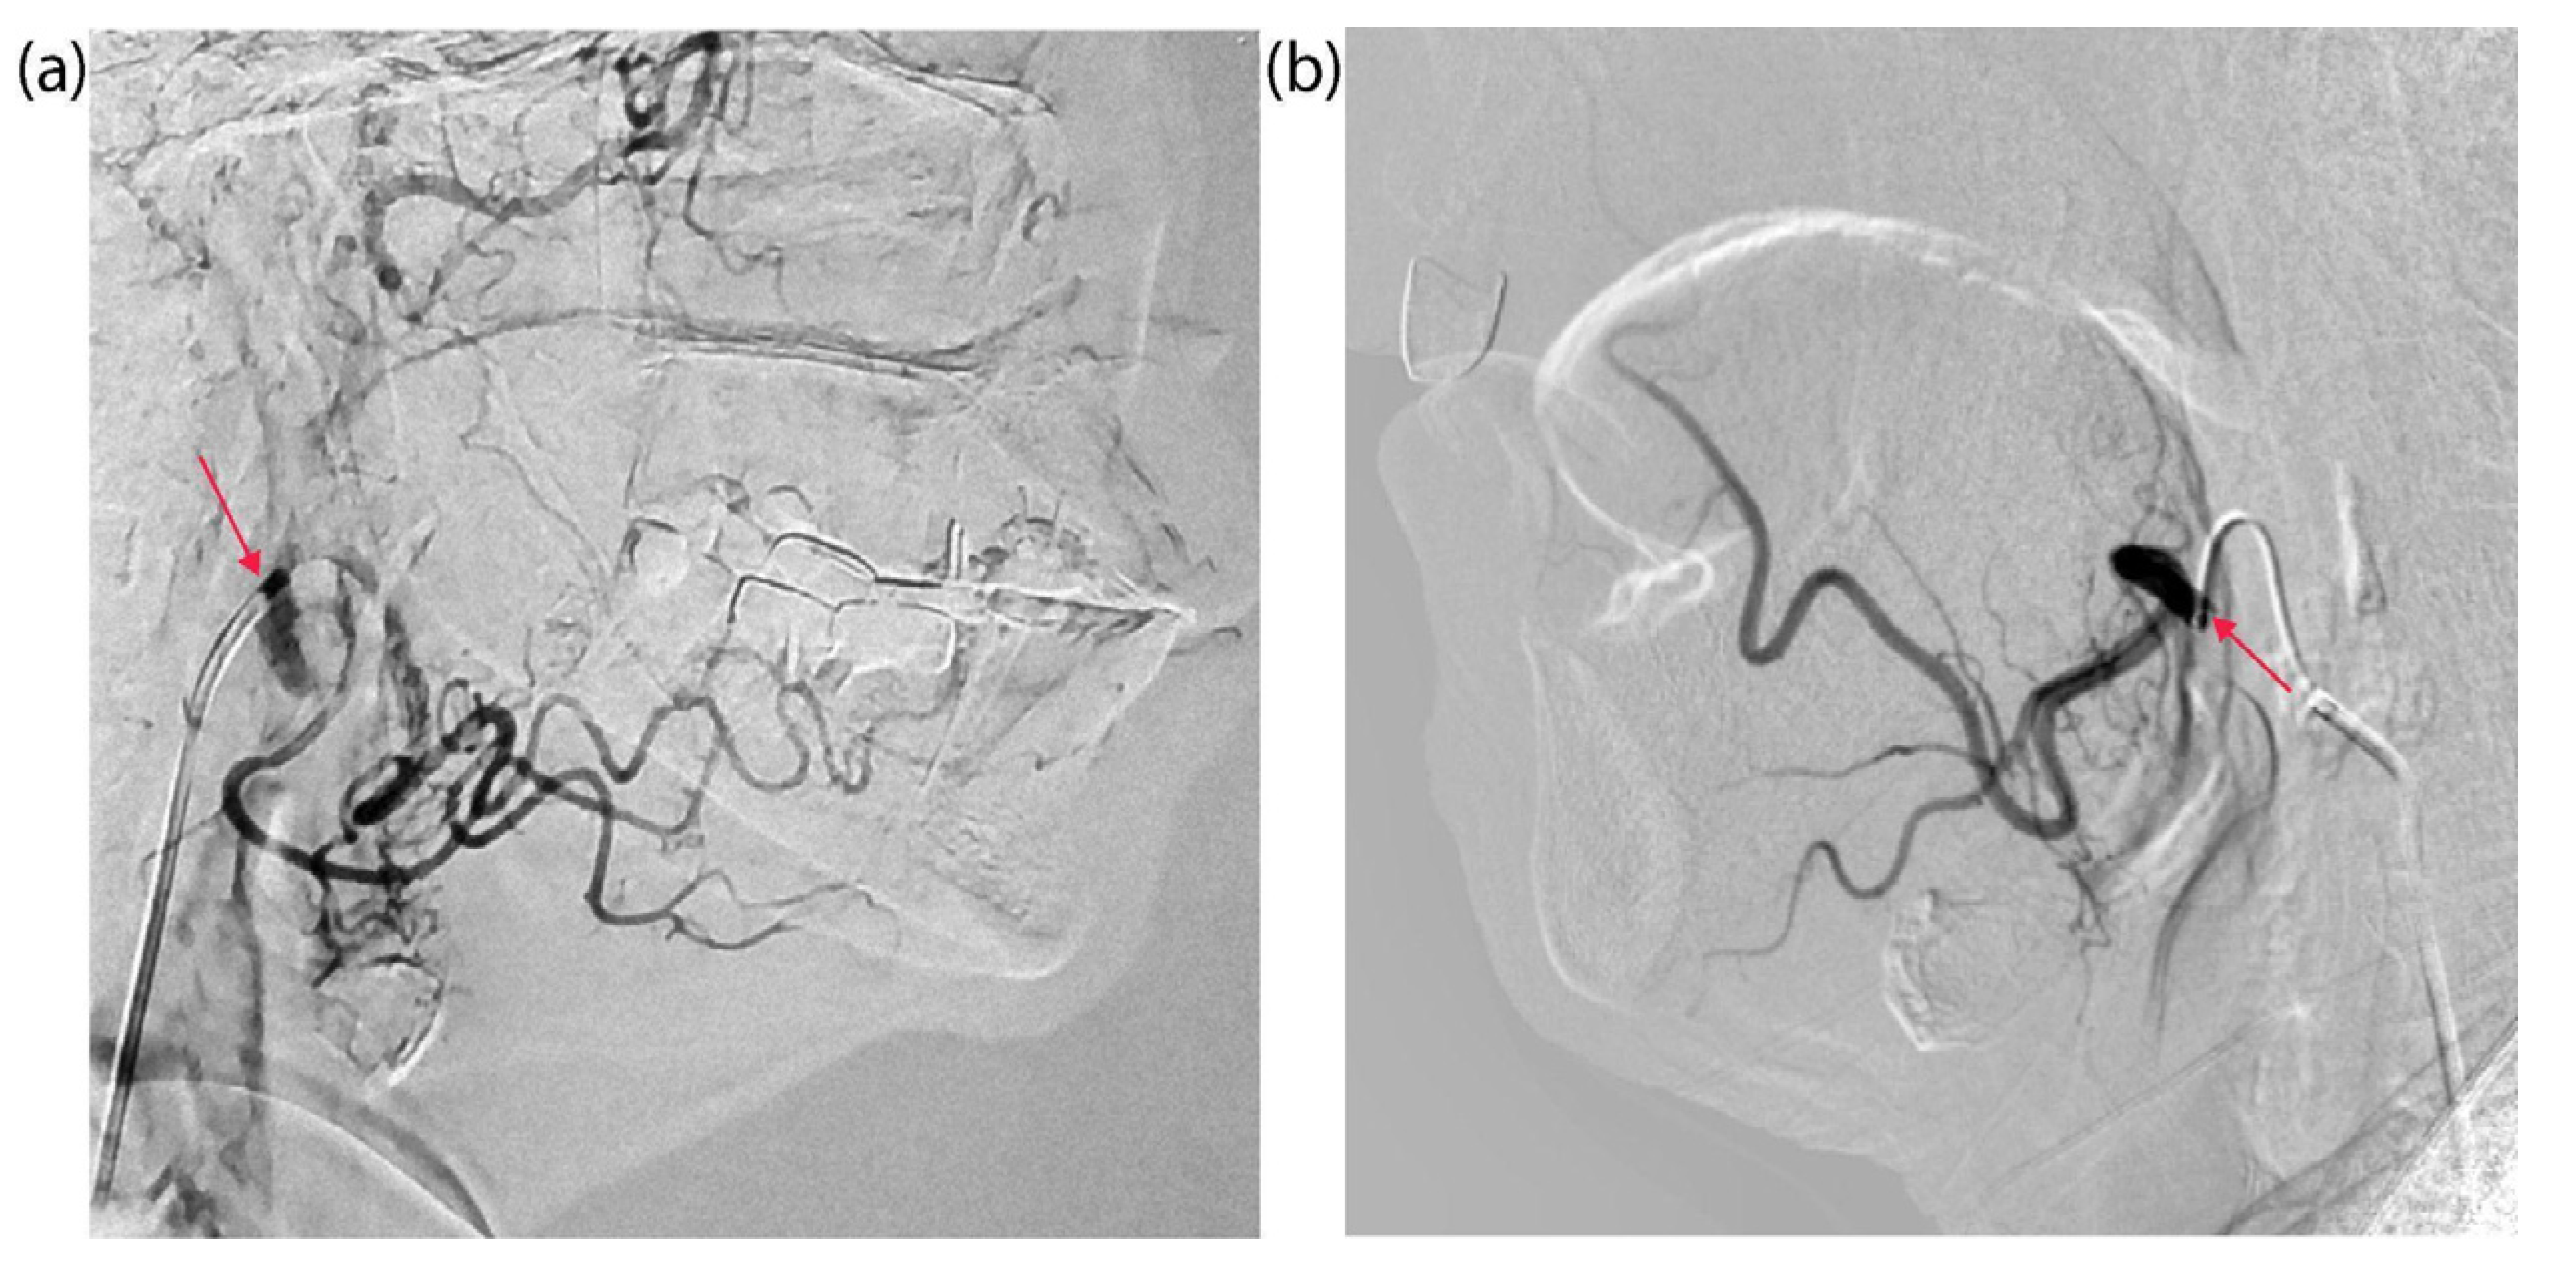

4.2. Tumor Catheterization